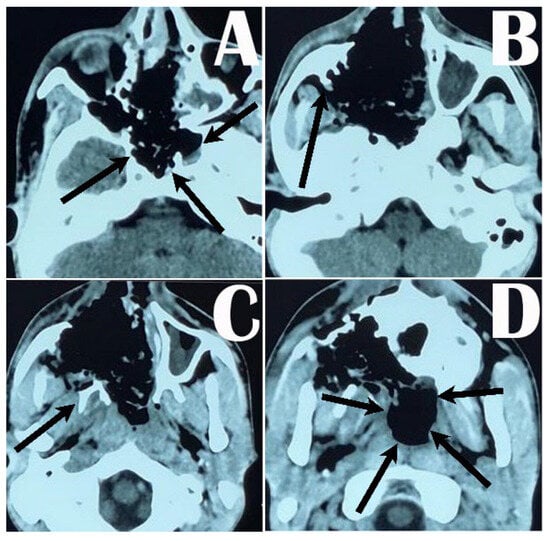

| Case 1 M/17 Y | Stage V | Multilobulated mass occupying the nasopharynx, sphenopalatine fossa, maxillary fossa, right nasal cavity | endoscopic, endonasal, trans maxillary pterygoid approach and middle fossa approach | partial removal | Facial swelling |

| Case 2 M/26 Y | Stage IV | Multilobulated mass occupying the nasopharynx, sphenopalatine fossa, maxillary fossa, right nasal cavity with superior orbital fissure and cavernous sinus | endoscopic, endonasal, trans maxillary pterygoid approach and middle fossa approach | partial removal | Epistaxis |

| Case 3 M/18 Y | Stage V | Multilobulated mass occupying the nasopharynx, sphenopalatine fossa, maxillary fossa, left nasal cavity | endoscopic, endonasal, trans maxillary pterygoid approach and middle fossa approach | partial removal | Epistaxis, facial swelling |

| Case 4 M/16 Y | Stage IV | Multilobulated mass occupying the nasopharynx, sphenopalatine fossa, maxillary fossa, right nasal cavity with superior orbital fissure and cavernous sinus | endoscopic, endonasal, trans maxillary pterygoid approach and middle fossa approach | total removal | Epistaxis, nasal deformity |

| Case 5 M/17 Y | Stage V | Multilobulated mass occupying the nasopharynx, sphenopalatine fossa, maxillary fossa, right nasal cavity with superior orbital fissure and cavernous sinus | endoscopic, endonasal, trans maxillary pterygoid approach and middle fossa approach | partial removal | No complication |

| Case 6 M/17 Y | Stage III | Multilobulated mass occupying the nasopharynx, sphenopalatine fossa, maxillary fossa, left nasal cavity | endoscopic, endonasal, trans maxillary pterygoid approach | partial removal | No complication |

| Case 7 M/17 Y | Stage V | Multilobulated mass occupying the nasopharynx, sphenopalatine fossa, maxillary fossa, right nasal cavity with superior orbital fissure and cavernous sinus | endoscopic, endonasal, trans maxillary pterygoid approach and middle fossa approach | total removal | Epistaxis, nasal deformity |

| Case 8 M/24 Y | Stage IV | Multilobulated mass occupying the nasopharynx, sphenopalatine fossa, maxillary fossa, right nasal cavity | endoscopic, endonasal, trans maxillary pterygoid approach and middle fossa approach | total removal | Epistaxis |

| Case 9 M/17 Y | Stage III | Multilobulated mass occupying the nasopharynx, sphenopalatine fossa, maxillary fossa, left nasal cavity | endoscopic, endonasal, trans maxillary pterygoid approach | total removal | Epistaxis, facial swelling |

| Case 10 M/16 Y | Stage IV | Multilobulated mass occupying the nasopharynx, sphenopalatine fossa, maxillary fossa, right nasal cavity with superior orbital fissure and cavernous sinus | endoscopic, endonasal, trans maxillary pterygoid approach and middle fossa approach | partial removal | No complication |

| Case 11 M/21 Y | Stage V | Multilobulated mass occupying the nasopharynx, sphenopalatine fossa, maxillary fossa, right nasal cavity | endoscopic, endonasal, trans maxillary pterygoid approach and middle fossa approach | total removal | No complication |

| Case 12 M/18 Y | Stage IV | Multilobulated mass occupying the nasopharynx, sphenopalatine fossa, maxillary fossa, left nasal cavity | endoscopic, endonasal, trans maxillary pterygoid approach and middle fossa approach | partial removal | Facial swelling |

| Case 13 M/18 Y | Stage III | Multilobulated mass occupying the nasopharynx, sphenopalatine fossa, maxillary fossa, right nasal cavity with superior orbital fissure and cavernous sinus | endoscopic, endonasal, trans maxillary pterygoid approach | total removal | No complication |

| Case 14 M/16 Y | Stage IV | Multilobulated mass occupying the nasopharynx, sphenopalatine fossa, maxillary fossa, right nasal cavity | endoscopic, endonasal, trans maxillary pterygoid approach and middle fossa approach | total removal | No complication |

| Case 15 M/17 Y | Stage V | Multilobulated mass occupying the nasopharynx, sphenopalatine fossa, maxillary fossa, right nasal cavity with superior orbital fissure and cavernous sinus | endoscopic, endonasal, trans maxillary pterygoid approach and middle fossa approach | total removal | No complication |